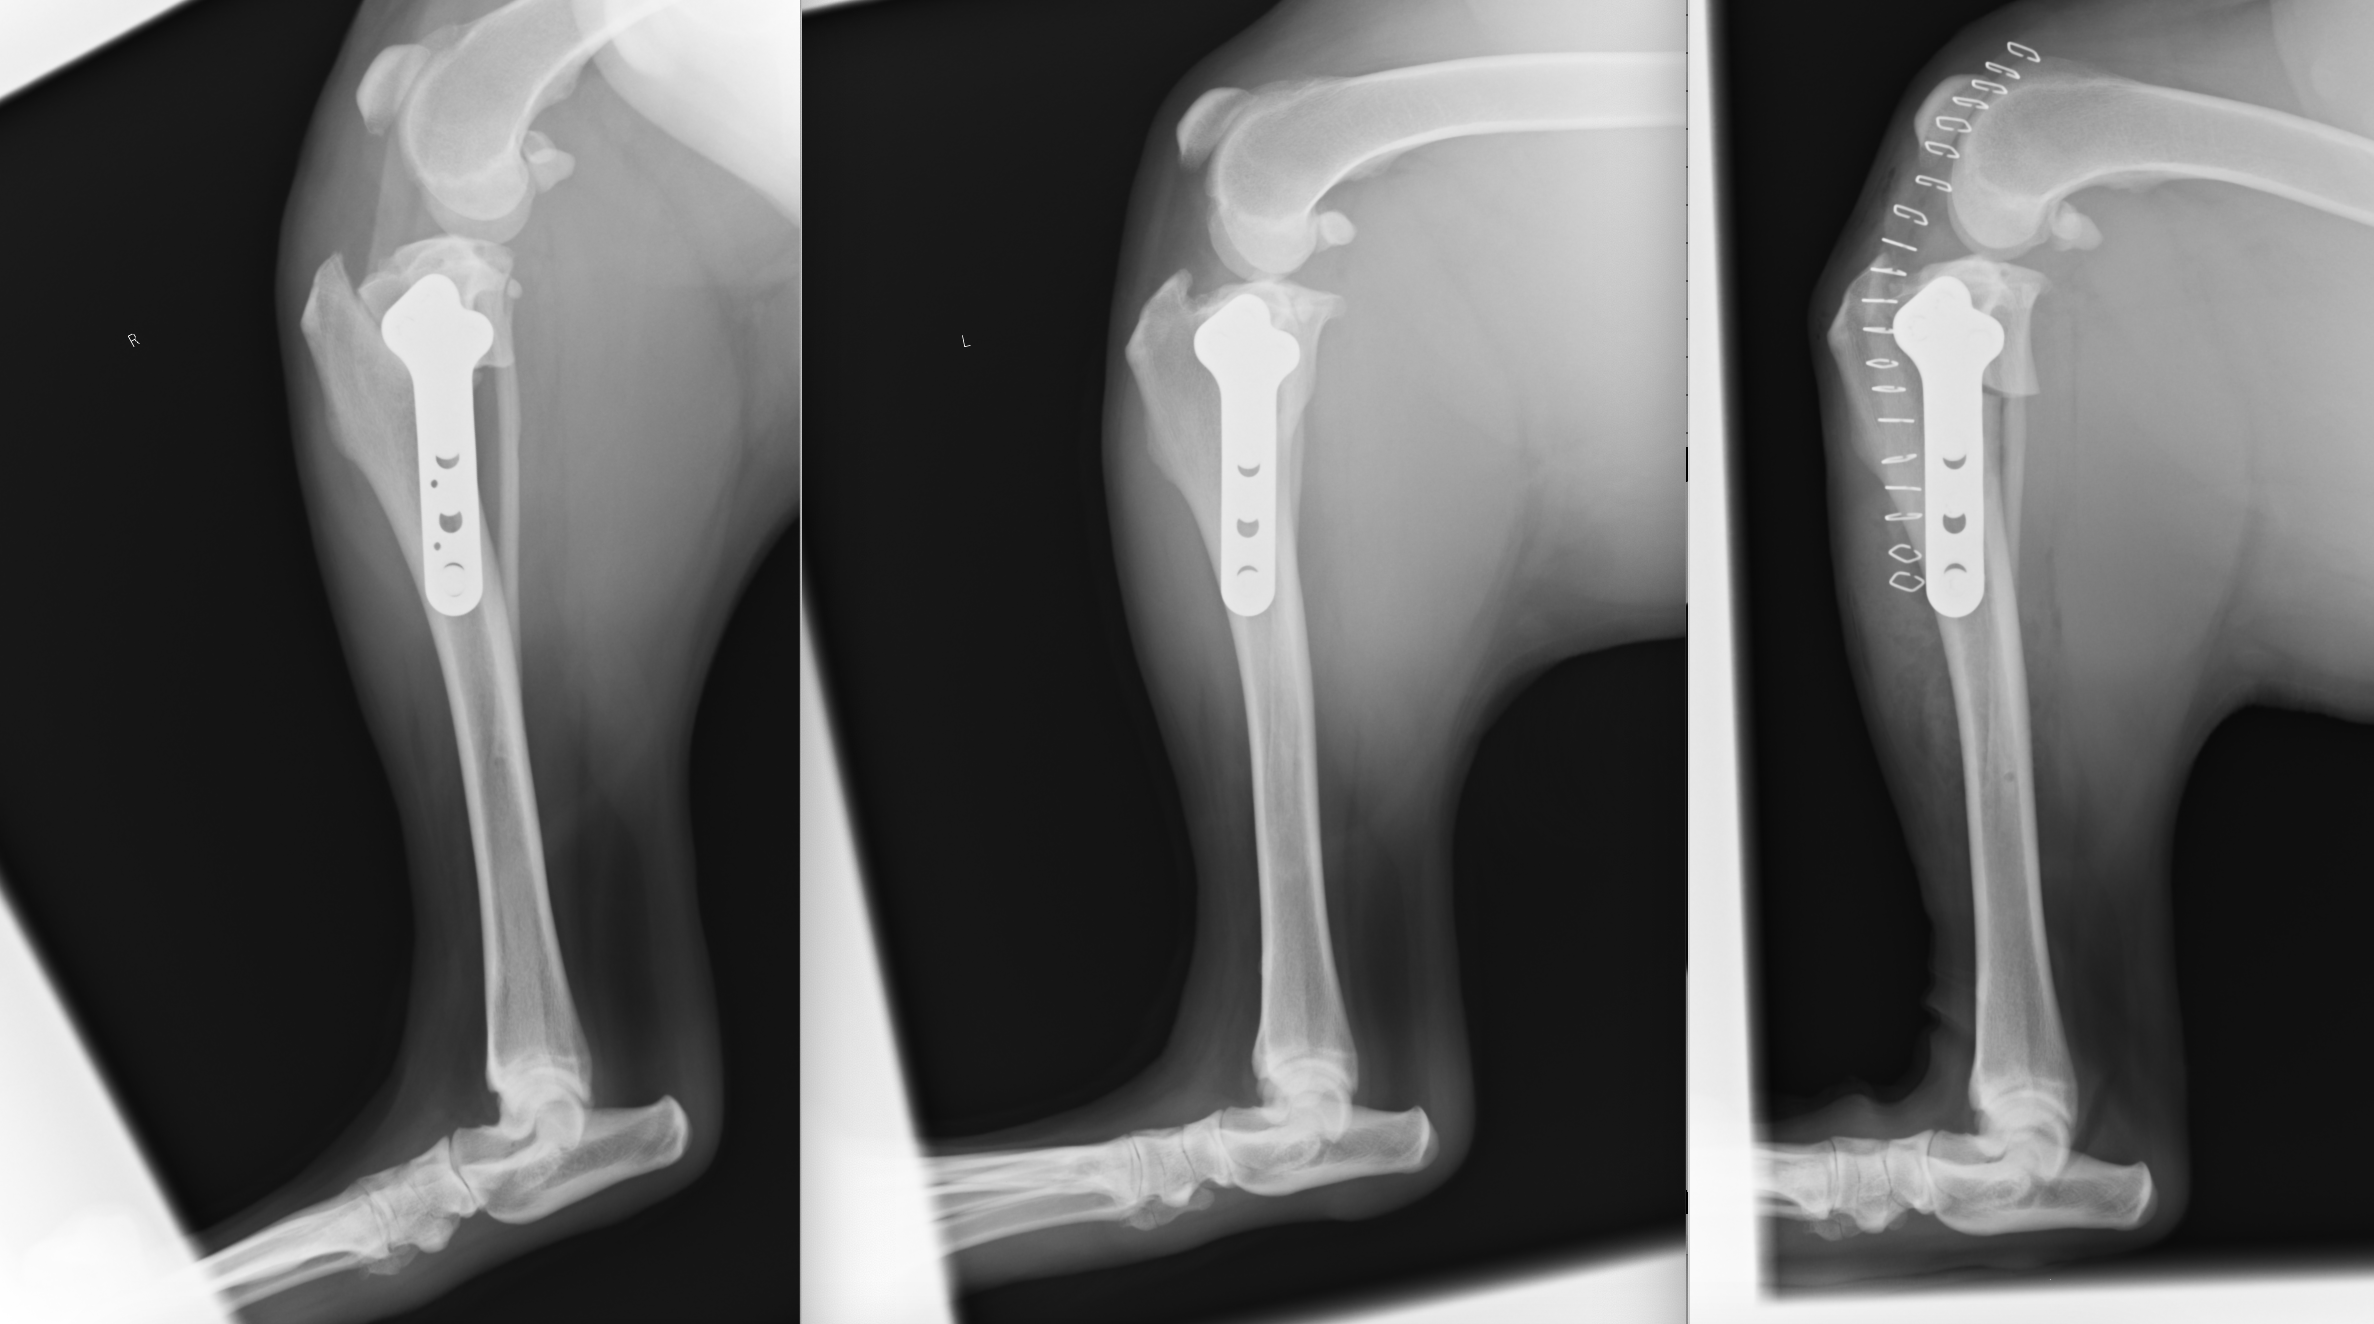

30kgの黒ラブの症例です。一番右のレントゲンが最初に行った手術です。半年後には反対側も切ってしまい、同様に手術しています(一番左)。真ん中は右の術後半年のレントゲンです。骨切部分がくっついているのがわかると思います。このように左右ともに切れてしまうケースも多いです。